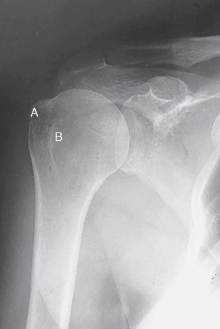

label the anatomy accordingly A-G, the projection/part, and rotation if applicable

head of humerus, greater tubercle, intertubercular sulcus, lesser tubercle, anatomic neck, surgical neck, body

AP shoulder — external rotation